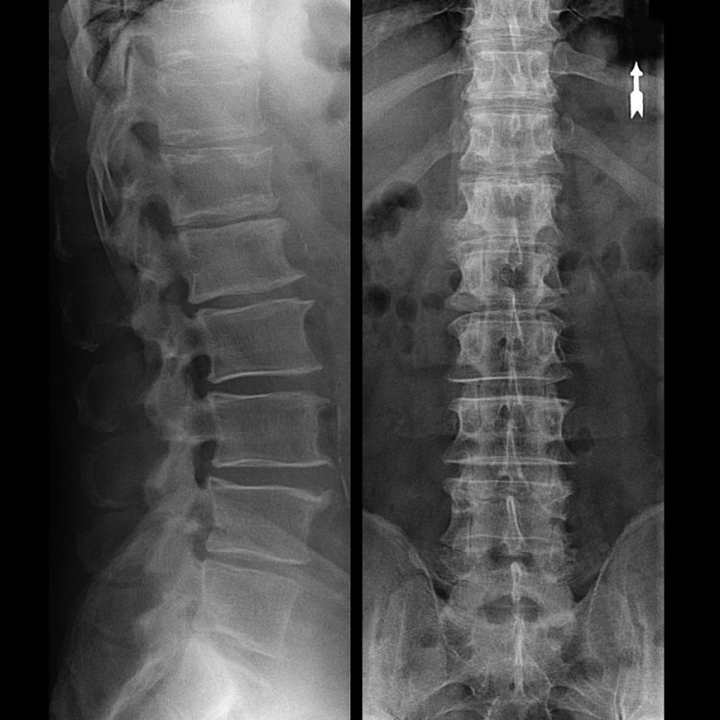

Kakla mugurkaula “rentgens” un pat ar funkcionāliem lieces un pagarinājuma testiem neuzrāda skrimšļus, jo to audi pārraida rentgena starus. Neskatoties uz to, pamatojoties uz skriemeļu atrašanās vietu, var izdarīt vispārīgus secinājumus par starpskriemeļu disku augstumu, vispārējo kakla fizioloģiskā izliekuma iztaisnošanu - lordozi, kā arī par marginālu izaugumu klātbūtni uz skriemeļiem ar ilgstošu to virsmu kairinājumu ar trausliem un dehidrētiem starpskriemeļu diskiem. Funkcionālie testi var apstiprināt mugurkaula kakla daļas nestabilitātes diagnozi.

Tā kā pašus diskus var redzēt tikai, izmantojot CT vai MRI, ir indicēta magnētiskā rezonanse un rentgena datortomogrāfija, lai noskaidrotu skrimšļa iekšējo struktūru un veidojumus, piemēram, izvirzījumus un trūces. Tādējādi ar šo metožu palīdzību tiek precīzi noteikta diagnoze, un tomogrāfijas rezultāts ir indikācija un pat aktuāls ceļvedis trūces ķirurģiskai ārstēšanai neiroķirurģijas nodaļā.